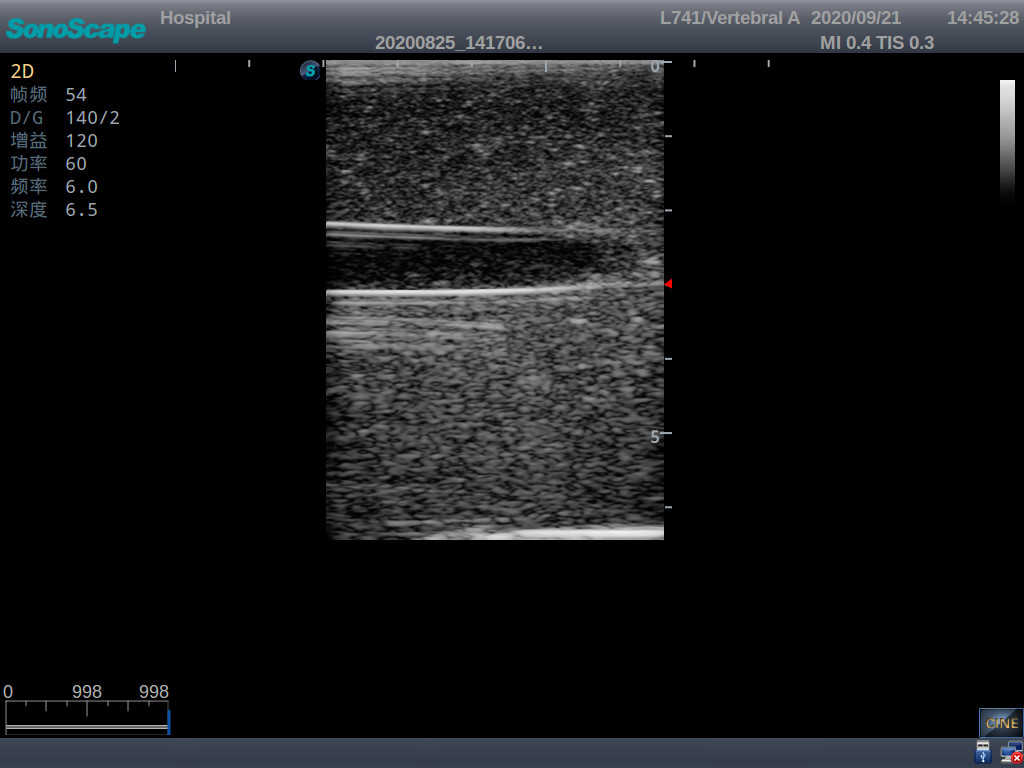

Vascular Access Ultrasound Training Model

Model TYE4034

Product size(mm) 170×130×65

Outline

The model is designed for simulating skin and arteriovenous puncture. It contains an artery and a vena comitans. Trainees can practice arteriovenous identification, arteriopuncture and venipuncture.

Skills Gained

· Arteriovenous identification

· Arteriopuncture

· Venipuncture

· Vascular access

Features

1) Made of high molecular polymer ultrasound material, close to real skin. It can conduct ultrasound-guided puncture exercises with various clinical models of real ultrasound machines

2) Clear and real images of arteries and veins

3) Showing physiological phenomena that veins are easier to be flatted than arteries under external pressure

4) When conducting vascular puncture, the piercing can be truly felt

5) Externally connected with the arterial pulsation ball, which can simulate the arterial pulsation as needed and make the puncture environment more realistic

6) The simulated arteries and veins are respectively externally connected with water bags, ensuring the liquid can be continuously extracted